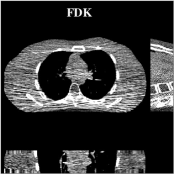

Image reconstruction methods have undergone significant advances over the past few decades, with different paths for various modalities. These advances can be broadly grouped in four categories of methods. The first category consists of analytical and algebraic methods. These methods include the classical filtered back-projection (FBP) methods for X-ray CT (e.g., Feldkamp-Davis-Kress or FDK method [1]) and the inverse Fast Fourier transform and extensions such as the Nonuniform Fast Fourier Transform (NUFFT) [2, 3] for MRI and CT. These methods are based on relatively simple mathematical models of the imaging systems, and although they have efficient and fast implementations, they suffer from suboptimal properties such as poor resolution-noise trade-off for CT.

Recent works applied learned unions of transforms to other applications. For example, the union of transforms model was pre-learned (from a dataset) and used in a clustering-based low-dose 3D CT reconstruction scheme [26]. Fig. 4 shows an example of high quality reconstructions obtained with this scheme. While the work used a PWLS-type reconstruction cost, a more recent method [132] replaced the weighted least squares data-fidelity term with the shifted-Poisson likelihood penalty, which further improved image quality and reduced bias in the reconstruction in ultra low-dose settings. Other recent works combined learned union of transforms models with material image models and applied it to image-domain material decomposition in dual-energy CT with high quality results [137, 138].